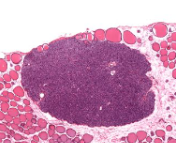

lymph node

clumps/clusters

region of organ

cortex of lymph node

(structure)

nodules